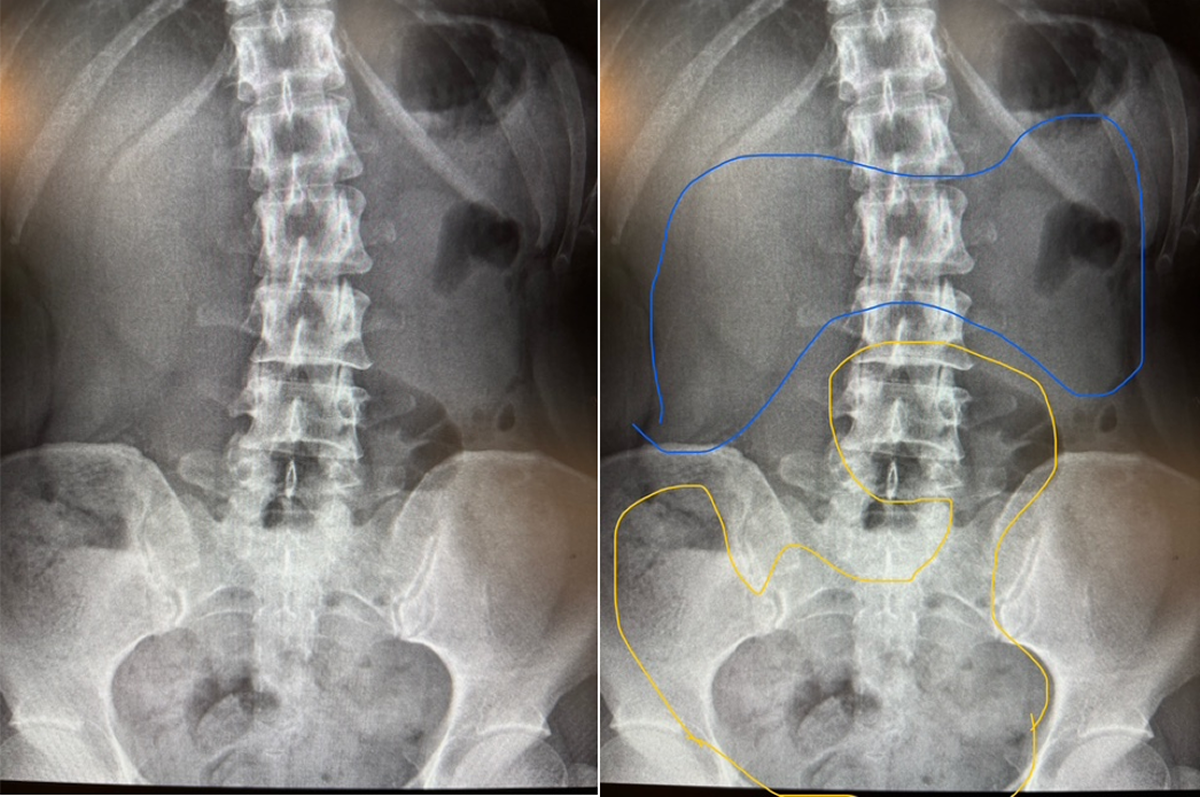

≪落下腸・立位≫

横行結腸(黄色枠線内)が骨盤内まで落ち込み、本来あるべき位置(青色枠線)は空っぽに。